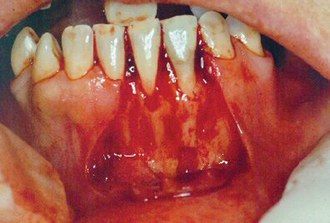

The viability of a mucoperiosteal flap depends on the blood supply from the base of the flap in the buccal sulcus. The flap is designed with a broad base to ensure an adequate blood supply. Relieving incisions are made deep enough into the sulcus to provide access to the periapical tissues (Fig. 6.6), and the incisions cut through oral mucosa and periosteum down to bone. The margins of the flap will rest on sound bone after surgery is completed; otherwise an unsightly dehiscence might develop (i.e. breakdown of the soft tissue, exposing underlying bone or root).

image

Fig. 6.6 A three-sided flap raised for apicectomy of lower incisors. The flap is reflected well beyond the apices to gain sufficient access.

There are three principal flap designs for surgical endodontics (Fig. 6.7):

Fig. 6.7 (a) A two-sided flap, with a broad base and a gingival margin incision that can be extended around the gingival margin. (b) A three-sided flap, with divergent relieving incisions. (c) The Luebke-Ochsenbein flap, which aims to combine the benefit of avoiding the gingival margin, with the access provided by a three-sided flap. (d) The semilunar flap.

See also Chapter 4, pages 37–38.

‘Two-sided’ flap

A relieving incision is made in the oral mucosa of the buccal sulcus, and the incision is extended around the gingival margin of the tooth to be treated (Fig. 6.7a). Preservation of the gingival attachment is preferred wherever possible. An advantage of this type of incision is the ease of repositioning of the flap after surgery. In most circumstances access to the apical tissues is satisfactory. If access is not sufficient, the gingival margin incision can be extended distally as far as is required, but failing that, a second relieving incision may be used; the flap is now a three-sided design.

‘Three-sided’ (trapezoidal) flap

The three-sided flap (Figs 6.6, 6.7b) provides excellent access for most surgical endodontic procedures. There should be no undue tension on the flap while it is being retracted.

A modification of the three-sided flap leaves a 3- to 4-mm rim of gingival tissue in situ. This design (the so-called Luebke-Ochsenbein flap design) usually provides satisfactory access to the apical tissues (Fig. 6.7c). Although this flap is prone to wound dehiscence, it usually gives a good aesthetic result.

Semilunar flap

The semilunar design avoids the gingival margin, and there is less risk of recession of the gingival tissues after surgery (Fig. 6.7d). However, there are three main disadvantages of the semilunar flap design:

surgical access to the apical tissues may be restricted

it is often difficult to ensure the incision line ends up resting on bone

the flap sometimes results in wound dehiscence.